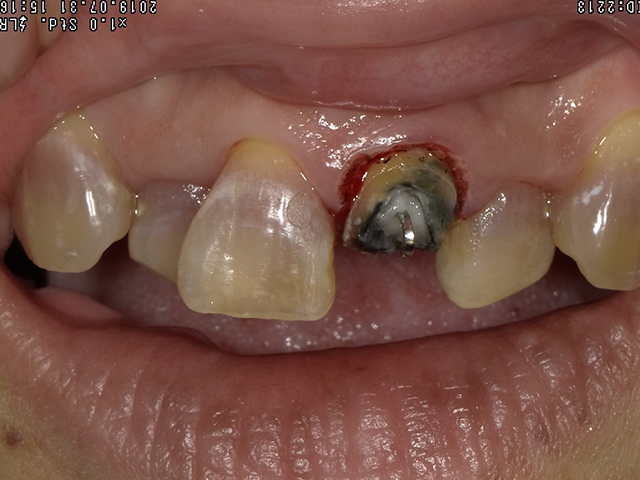

- 根っこの治療を行い、土台部分に針金でフックをかけます。

この上に仕掛け付きの仮歯を装着してゴムの力で引っ張ります。

仮歯がしっかり入るため外からの見た目も気にせず引っ張ることができます。

- 何度かゴムを調整し、ご自身の歯が出てきました。

一緒に歯周靭帯がついてきているので、この歯周靭帯を切除し歯茎が安定するのを待ちます。

この間も仮歯があるため見た目を気にせず過ごしていただけます。